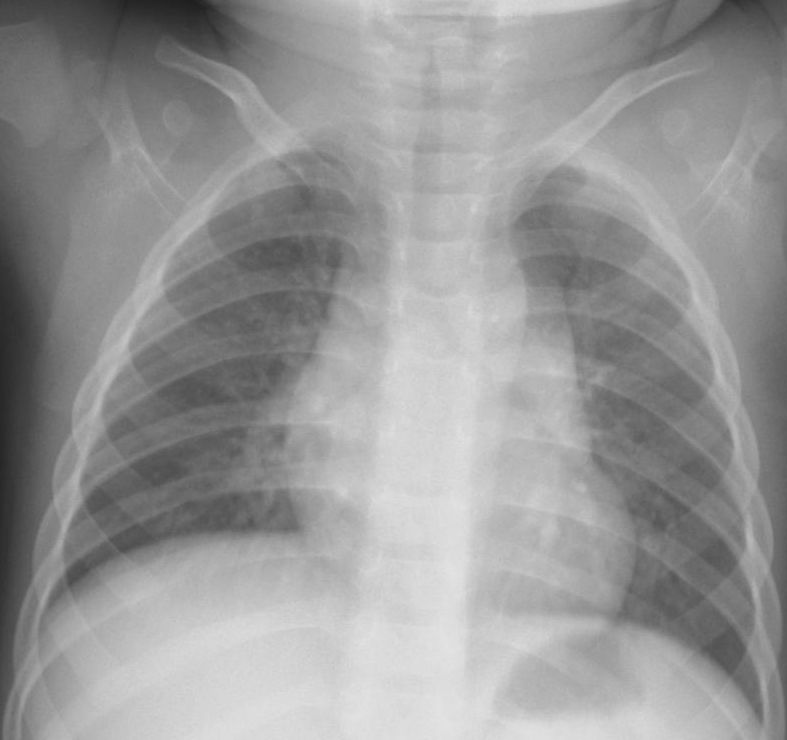

新生児・乳幼児によくみとめられるサイン。いずれも前縦隔にある胸腺を示している。胸腺は免疫器官として重要で、生後活発に活動しているため、この年齢では大きく、他の縦隔腫瘍と鑑別するのに役立つ。肋骨に圧迫されて波打つような形状がtjymic wave sign 、帆のように三角に突出してみえるのが sail sign 。

[参考例] ①透過性不良の間質性肺炎を示唆する写真だが、sail signをみとめる。同時に気管が右へ弯曲している。正面像で撮影できていないが、実際の臨床の場ではこのようなレントゲン像が少なくなく、読影に影響されてはいけない。 [参考例] ②右肺への張り出した陰影に肋骨部の凹みがあり胸腺と判断できる。 [参考例] ③縦隔の拡大があり右辺縁はwaveしていて胸腺と理解できる。(左肺野に浸潤影をみとめシルエットサイン陽性) [参考例] ④胸腺の典型例 epicardial fat(心臓横隔膜の脂肪組織) 心臓には脂肪組織が沈着していてレントゲン像として左右の心臓下部に均等な陰影として出現。右側には下大静脈の陰影もみとめるので銘記しておくとよい。 beginner’s triangle(正常でも異常に見えやすい右下肺内側のこと)(medicina Vol. 50 No.12 2013-11 一色論文 )。